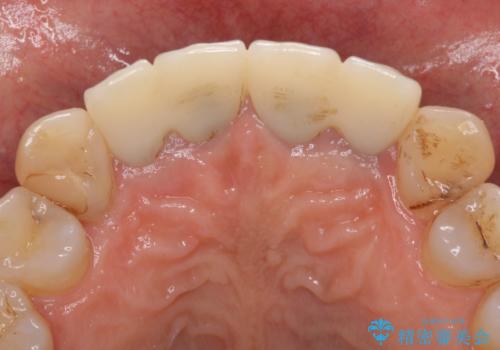

- 昨年治療した前歯の根尖部に痛みを感じ、ラバーダムや顕微鏡を用いた根管治療を希望されて、転院された患者様です。

前医にて神経を取り除いた処置を行った際、ラバーダムが使用されなかったとのことで転院されてきました。

根管治療を実施した後、オールセラミッククラウンに補綴することとしました。